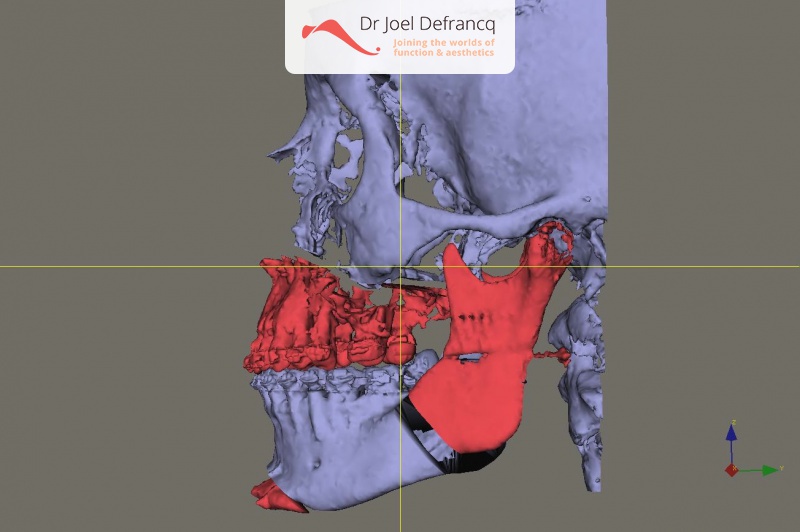

Kaakchirurgie

- Verlenging onderkaak (BSSO)

- Verlenging bovenkaak (Le Fort I)

- Vertikale verlenging bovenkaak (Le Fort I)

- Kinchirurgie

- Redo